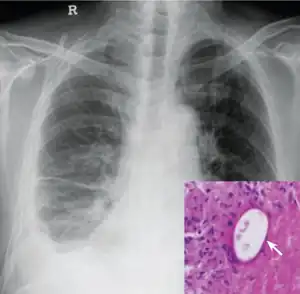

The most prominent species of Paragonimus in human medicine is Paragonimus westermani, an infectious lung fluke originating in eastern Asia. Worldwide, about nine species of Paragonimus are known to cause human paragonimiasis in which many of the species reside in East Asia, West Africa, and in North and South America.[4]

Infection

Symptoms of paragonimiasis may include abdominal pain, diarrhea, fever, and hives. If the infection remains untreated, the symptoms may diminish or disappear after only few months, but sometimes they last for decades.[6] Paragonimiasis is caused by the body's natural immune response to the worms and eggs that are present and also migrating from the intestines to the lungs.

As a rule, the parasites begin to cause symptoms about three weeks after ingesting live metacercariae. After about eight weeks, they begin to produce eggs in the lungs. Some patients develop brain damage if parasites establish in the brain and produce eggs. The brain damage commonly causes headache, vomiting, and seizures.[4] Untreated cerebral paragonimaisis commonly results in death from increased intracranial pressure.